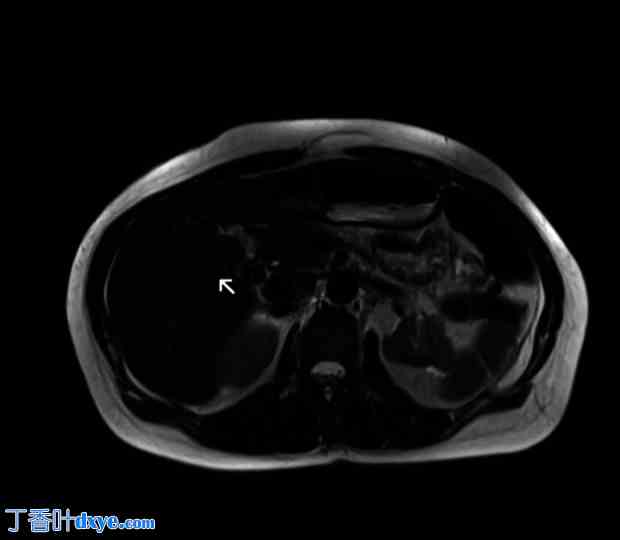

一名 42 岁女性因急性胰腺炎入院。她既往病史包括小肠切除术、子宫切除术及附件切除术、肠系膜淋巴结切除术、阑尾切除术和因神经内分泌肿瘤 (NET) 而进行的网膜切除术。她还接受过生长抑素治疗,并因复发性肾结石放置了输尿管支架。她有复发性腹痛病史,在入住我院之前,3 个月前因急性胆源性胰腺炎转入另一家医院。临床检查:右腹部压痛,无其他腹部体征。血液检查显示白细胞 (WBC) 计数 12.65×103/uL,C 反应蛋白 (CRP) 0.57 mg/dl,脂肪酶 4230 U/l。急诊腹部CT扫描显示胆囊和胆道内有微结石,胆管壁增厚(图1)。考虑到胆道内可能存在CT未显示的胆结石,作者进行了T2加权磁共振胰胆管造影(MRCP),结果显示胆囊胆总管结石(图2)。然而,只有3D冠状位重建图像才怀疑胆囊异常(图3)。

图2.

术前检查。在T1加权序列中,磁共振胰胆管造影证实了胆囊胆总管结石的存在。